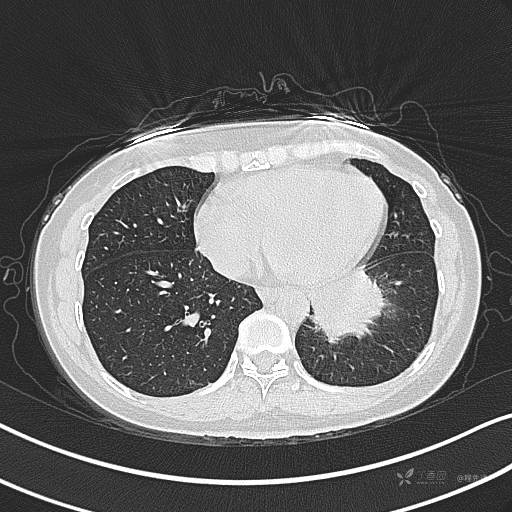

CT平扫

肺窗